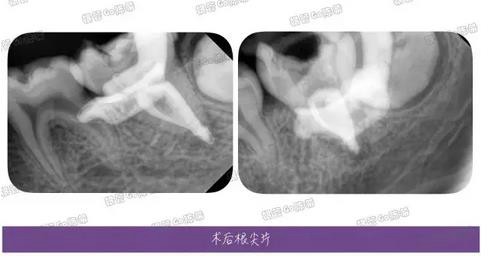

完成充填后的多角度根尖片,檢查根充效果,之前有幾個(gè)病例糊劑超填得明顯,所以做了一定的改正。

這例看來是控制得稍微好點(diǎn)了,繼續(xù)努力~